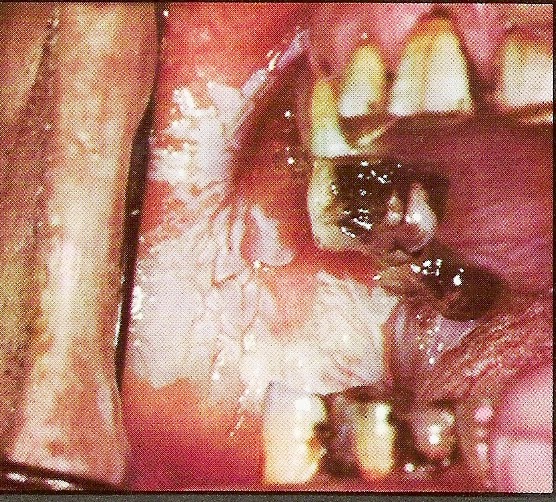

Λευκοπλακία, μια προκαρκινική βλάβη στο στόμα που πρέπει να αφαιρείται

Η λευκοπλακία είναι μία μη ειδική λευκή πλάκα, πάχους 1-5 χιλιοστά ή και περισσότερο που είναι στερεά προσκολλημένη στους ιστούς του στόματος.

Η επιφάνειά της μπορεί να είναι ομαλή ή ανώμαλη (αυλακωτή ή κοκκιώδης) καμιά φορά δε παρουσιάζει εξέλκωση (πληγή).